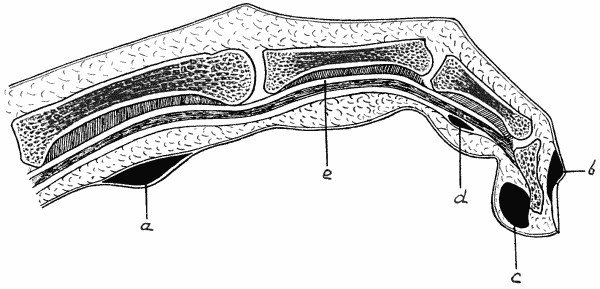

| 9. | Diagram of various forms of Whitlow | 56 |